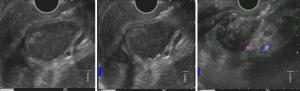

Patient 1, a 63-year-old female, underwent surgery and adjuvant therapy for colon cancer in 2018. In 2020, a cystic lesion measuring 15 mm × 16 mm was detected in the body of the pancreas on a CT scan (Figure 2).

During a routine examination in November 2023, it was discovered that the lesion had increased by 5 mm in each dimension. Due to its proximity to the superior mesenteric artery and the associated risk of vascular injury, percutaneous biopsy and EUS-guided FNB were considered unsafe. However, EUS examination revealed that the lesion corresponded to type 1 intraductal papillary mucinous neoplasm (IPMN-I). DAB was conducted, revealing no atypical cells and a CEA level of 123.94 ng/mL. These findings suggested the lesion had minimal malignant potential, leading to the decision to continue patient observation instead of pursuing distal pancreatic resection initially considered. Twelve months later, a follow-up MRI indicated no clear connection with the main pancreatic duct, as well as absence of lymphadenopathy and signs of contrast accumulation in the lesion.